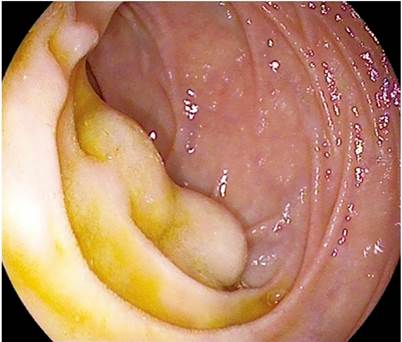

Acude a la unidad de endoscopias para realizar una endoscopia digestiva alta (EDA) para cribado de varices. Durante la exploración se identifica, en la segunda porción duodenal distalmente a la papila duodenal, dos lesiones nodulares de aspecto subepitelial de unos 10 mm recubiertas de mucosa normal (Figura 1). Con intención diagnóstica se realiza biopsia sobre biopsia de una de ellas, lo que provoca un sangrado babeante persistente, que requiere colocar un hemoclip para conseguir hemostasia. No se identifican otras lesiones ni datos de hipertensión portal.